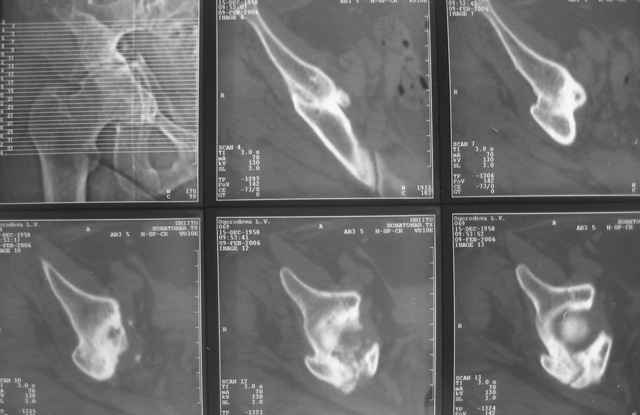

Ув.коллеги,нужен совет по представленному случаю. Пациентка, 50лет. В 2003 году в результате дтп получила перелом вертлужной впадины. 1.5 месяца находилась на скелетном вытяжении, в дальнейшем до 10 месяцев после травмы ходила без опоры на конечность. Вернулась к труду, но в 2006 году перешла на инвалидность и была поставлена в областную очередь эндопротезирования. В данный момент уже находится в отделении, но, судя по рентгенограммам и данным КТ, сращения на уровне перелома не произошло. Что предпочесть? 1.Остеосинтез с костной пластикой и последующим эндопротезированием. 2."Октопус". 3.Кольцо Мюллера. Заранее благодарен за ответы и ценные замечания.

при более внимательном анализе КТ, передняя колонна выглядит сросшейся, остается синтезировать заднюю?Похоже был низкий двухколонный перелом или перелом передней с задним полупоперечником?